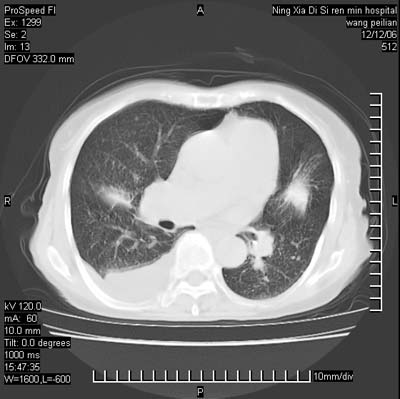

标题: CT5609:胸部:女77 病史不详

两肺可见多个大小不等的结节,左侧有胸水,纵隔淋巴结增大,考虑是细支气管肺泡癌

两肺尖纤维索状影,两下肺结节块状影,且有钙化灶,右胸腔积液。考虑肺结核并胸膜炎。

两肺尖纤维索状影,两下肺结节块状影,且有钙化灶,右胸腔积液。考虑肺结核并胸膜炎肺间质纤维化

考虑:1、慢性支气管炎合并全小叶型肺气肿、间质纤维化;

2、双肺结核;

3、右侧胸膜炎(积液)。

1、双肺继发型肺结核(以纤维、增殖灶为主);

2、右侧胸腔积液;

3、其余符合老年肺改变。

双肺见多个结节状及条索状影,双侧胸腔积液,右侧叶间积液,考虑结核性胸膜炎